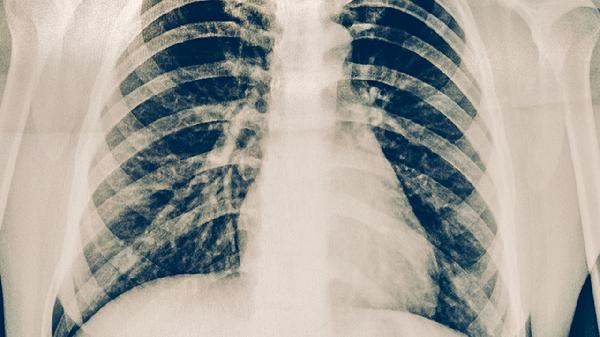

肋软骨炎一般不会转移疼痛,其特点为局部固定性疼痛。肋软骨炎是肋软骨与胸骨连接处的非特异性炎症,主要表现为前胸壁单侧或双侧局限性疼痛,可能伴随肿胀和压痛,疼痛通常不会放射至其他部位。

肋软骨炎的疼痛多呈钝痛或锐痛,在咳嗽、深呼吸、上肢活动时加重,按压病变部位可诱发明显压痛。疼痛位置固定于肋软骨交界处,常见于第2-5肋软骨,部分患者可能因炎症刺激周围神经出现牵涉痛,但并非真正的转移性疼痛。典型发作时疼痛可持续数周至数月,呈间歇性加重,但不会随病程进展改变疼痛区域。

极少数情况下,当肋软骨炎合并胸椎病变或神经根受压时,可能出现类似转移痛的放射性不适,此时需通过影像学检查排除其他疾病。若疼痛范围扩大或性质改变,需警惕带状疱疹、肋间神经痛、心源性疼痛等疾病可能。